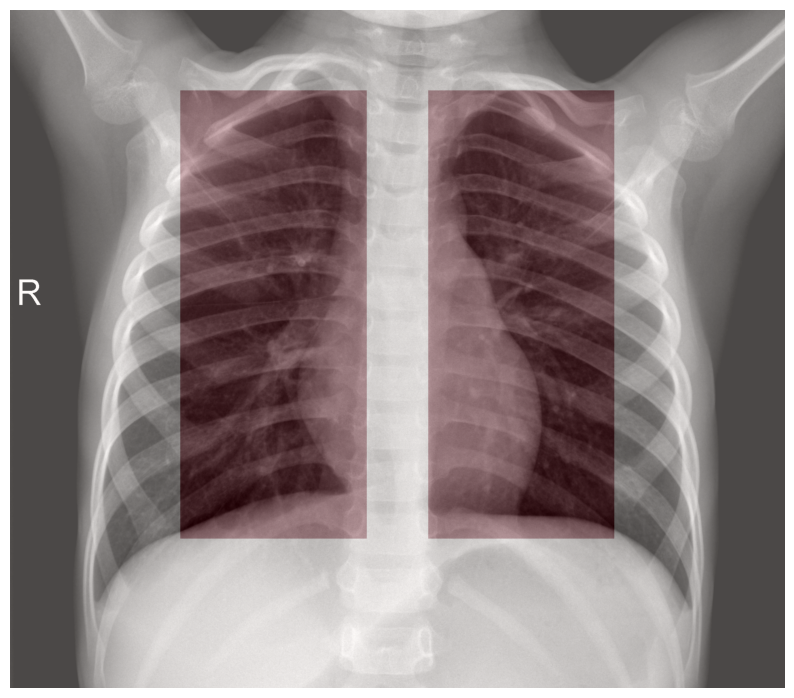

Chest X-ray imaging is commonly used to diagnose pneumonia, but accurately localizing the pneumonia-affected regions typically requires detailed pixel-level annotations, which are costly and time consuming to obtain. To address this limitation, this study proposes a weakly supervised deep learning framework for pneumonia classification and localization using Gradient-weighted Class Activation Mapping (Grad-CAM). Instead of relying on costly pixel-level annotations, the proposed method utilizes image-level labels to generate clinically meaningful heatmaps that highlight pneumonia-affected regions. Furthermore, we evaluate seven pre-trained deep learning models, including a Vision Transformer, under identical training conditions, using focal loss and patient-wise splits to prevent data leakage. Experimental results suggest that all models achieved high classification accuracy (96--98\%), with ResNet-18 and EfficientNet-B0 showing the best overall performance and MobileNet-V3 providing an efficient lightweight alternative. Grad-CAM heatmap visualizations confirm that the proposed methods focus on clinically relevant lung regions, supporting the use of explainable AI for radiological diagnostics. Overall, this work highlights the potential of weakly supervised, explainable models that enhance transparency and clinical trust in AI-assisted pneumonia screening.💡 Deep Analysis